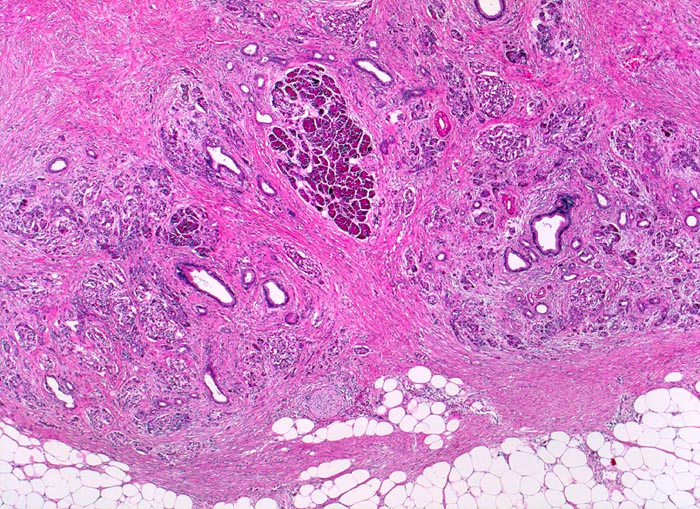

Chronisch-sklerosierende Pankreatitis

In der Übersicht ist die lobuläre Architektur des Pankreas erkennbar. Azini gruppieren sich um intralobuläre Gänge. Das Pankreasparenchym ist aufgesplittert durch eine dissoziierende Fibrose zwischen und innerhalb der Lobuli. Die Entzündung ist minimal ausgeprägt. Die Veränderungen sind herdförmig unterschiedlich schwer. Ein Lobulus scheint weitgehend unbehelligt. Zusammensinterung und Proliferation der inter- und intralobulären Duktuli.

Alkoholiker mit rezidivierten akuten Pankreatitisschüben. Chronische Diarrhoe.